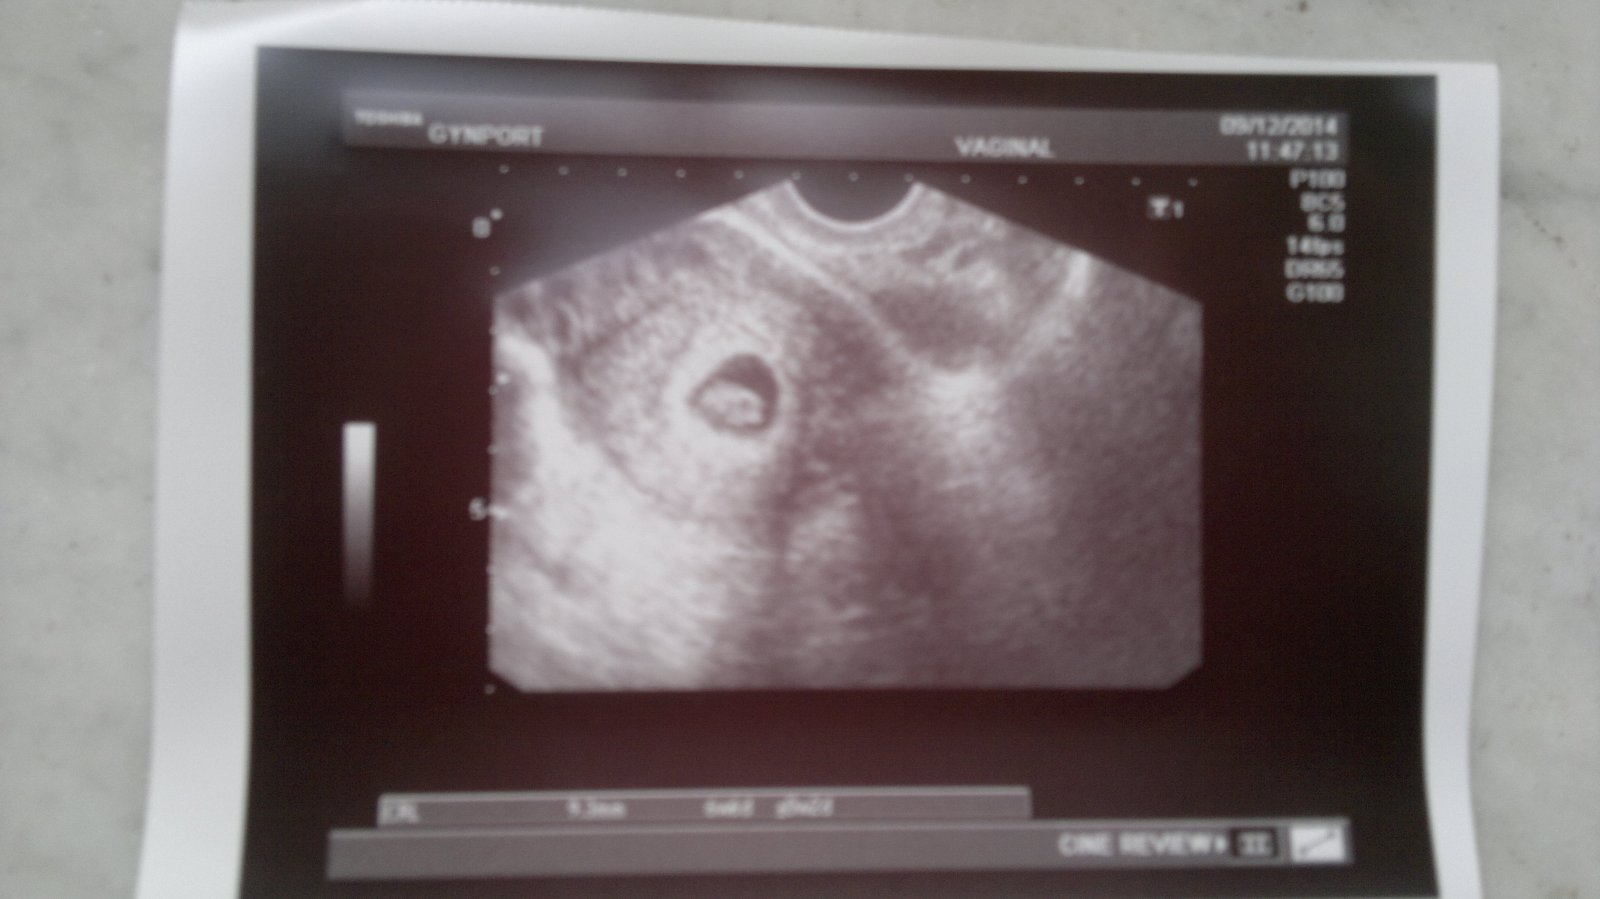

V 6tt je vidět jen gestační váček, měly jste to tak?

ahoj holky tak dneska jsem byla poprve na utz jsem 6 tt+ 0dni zatim byl videt jenom gestacni vacek 9mm,jinak nic meli jste to taky tak v 6 tydnu?vim ze tady jde o dny🙂ale hodne me rozhodila ,ze uz mi dala tehu prukazku,jen rekla tehotenstvi se vyviji dobre za dva tydny kontrola to uz bude srdicko prukazku muzeme dat uz dneska ..tohle jsem jeste nezazila,ze se dava tehu prukazka pred srdickem🙂vite jak se to rika,,aby se neco nezakriklo"